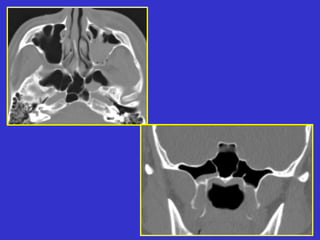

Este documento describe las diferentes proyecciones radiográficas utilizadas para examinar los senos paranasales, incluyendo las proyecciones básicas de Caldwell, Waters lateral y las proyecciones especiales como Hirtz y Waters mentonasal. También describe las diferentes estructuras anatómicas que componen el complejo ostiomeatal anterior y posterior de los senos paranasales.